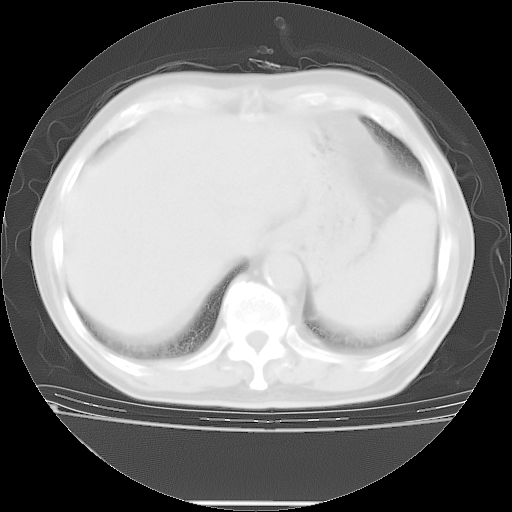

胸腹部CT,诊断意见:左上肺叶钙化灶、左侧胸膜局限性增厚并钙化、胆囊炎。描述部分肺组织呈磨玻璃样改变。

今天复查肺部CT,发现双肺广泛磨玻璃样改变。所以我把3月19日和5月9日相隔50天的肺部CT上传。请大家会诊。

5月9日肺部CT(在4月27日齐鲁医院肺部CT描述部分肺组织磨玻璃样改变,12天后肺组织广泛磨玻璃样改变)

大致读了系列胸部CT:纵隔窗无明显异常,肺窗:从4、27至今:主要是双肺中下野外带可见毛玻璃样改变,目前处于急性肺泡炎阶段,至于原因考虑1、结替组织或胶原血管性疾病所致?2、恶性疾病如恶组在肺部所致的表现或细支气管肺泡癌?3、药物或其它原因如肺蛋白沉着症所致肺泡炎目前不太可能?总之,明天就去请我院的呼吸科、感染科、血液科和临免专家会诊哈。